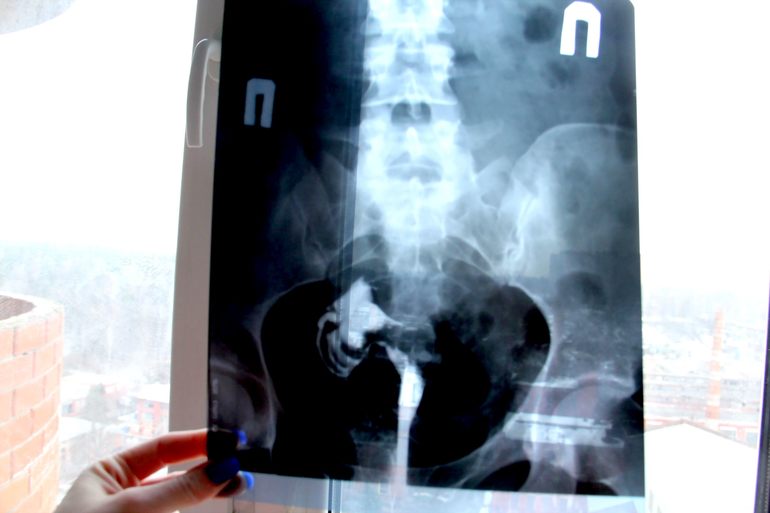

Снимок ГСГ

Вот снизу полоска пряма которая идет вверх это ваш контраст, матку не заметно тк затемнена но вот прямая линия и проходит через влагалище шейку и матку оттуда трубу светло сытно с левой стороны это и есть труба.

это ж рентген! откуда на нем матка, рентген мягкие ткани не отображает, вот у Вас кости и контрастное вещество

а по матке  контрастное вещество не должно было разлиться?

так оно там и есть, скопление посередине, матка ж очень маленькая

У вас левой нет трубы? Странновато. тоже не пойму матка то где...

левая труба удалена после первой ВБ

жидкость быстро излилась в полость трубы а из нее в брюшину пошла, то есть трубочка твоя хорошо проходима. В матке жидкость может застояться только когда проходимость частичная или ее нет. Снимок отображает то место, которое заполнено контрастом ))) Все отлично у тебя!